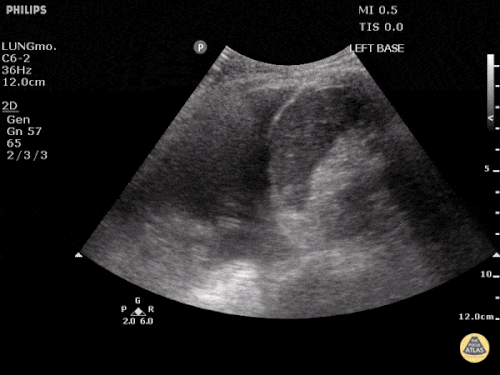

Question 3: You are called to evaluate a patient at a CATS call on M5. The patient is a 99-year-old man with diastolic dysfunction. His diuretics have been held for the past week due to renal dysfunction (currently his creatinine has plateaued at 4.8 mg/dL). He has been placed on BiPAP but continues having substantial work of breathing. The following images are obtained from his right thorax:

- Describe the ultrasonographic findings (Do you think this is a bird or a plane? Superman?)

- What is your diagnosis?

- What is the best therapeutic strategy for this patient?